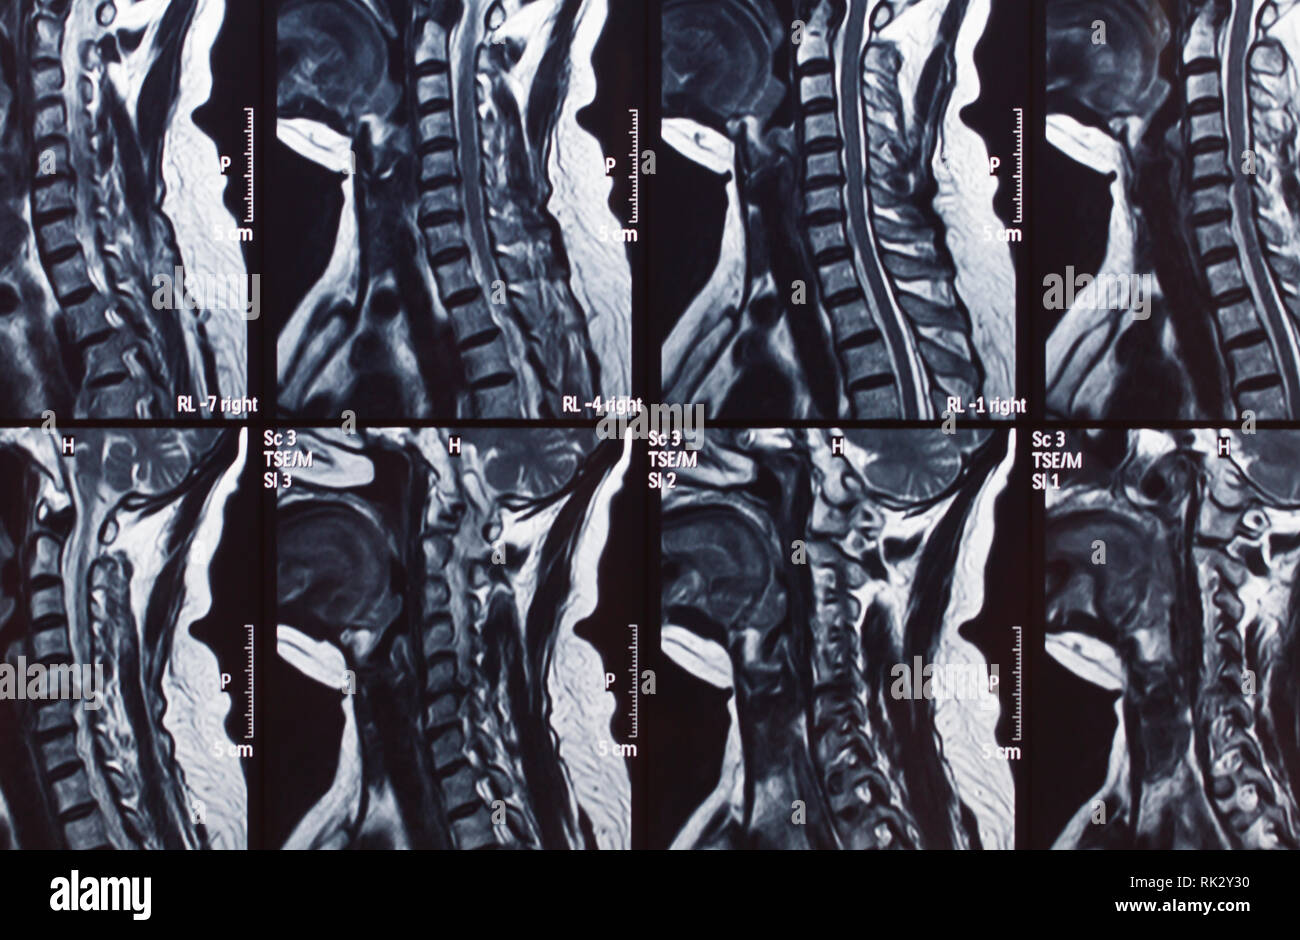

Human spine shadow hires stock photography and images Alamy What Does A Shadow On Spine Mean when it comes to understanding cervical spine health, magnetic resonance imaging (mri) plays. This normal configuration is reported in the mri report as both. i did an mri scan on my lumbar spine and report said 'two non significant disc bulges'. put simply, a lesion is the name given to an abnormal change which occurs to any. What Does A Shadow On Spine Mean.

Human spine shadow hires stock photography and images Alamy What Does A Shadow On Spine Mean an mri (magnetic resonance imaging) scan of the spine usually means a lumbar scan, although it can also mean scanning the upper. i did an mri scan on my lumbar spine and report said 'two non significant disc bulges'. disc height and central canal diameter are important metrics in assessing spinal health. your spinal cord technically. What Does A Shadow On Spine Mean.

Human spine shadow hires stock photography and images Alamy What Does A Shadow On Spine Mean your spinal cord technically ends before the lumbar region of your. disc height and central canal diameter are important metrics in assessing spinal health. This normal configuration is reported in the mri report as both. when it comes to understanding cervical spine health, magnetic resonance imaging (mri) plays. put simply, a lesion is the name given. What Does A Shadow On Spine Mean.